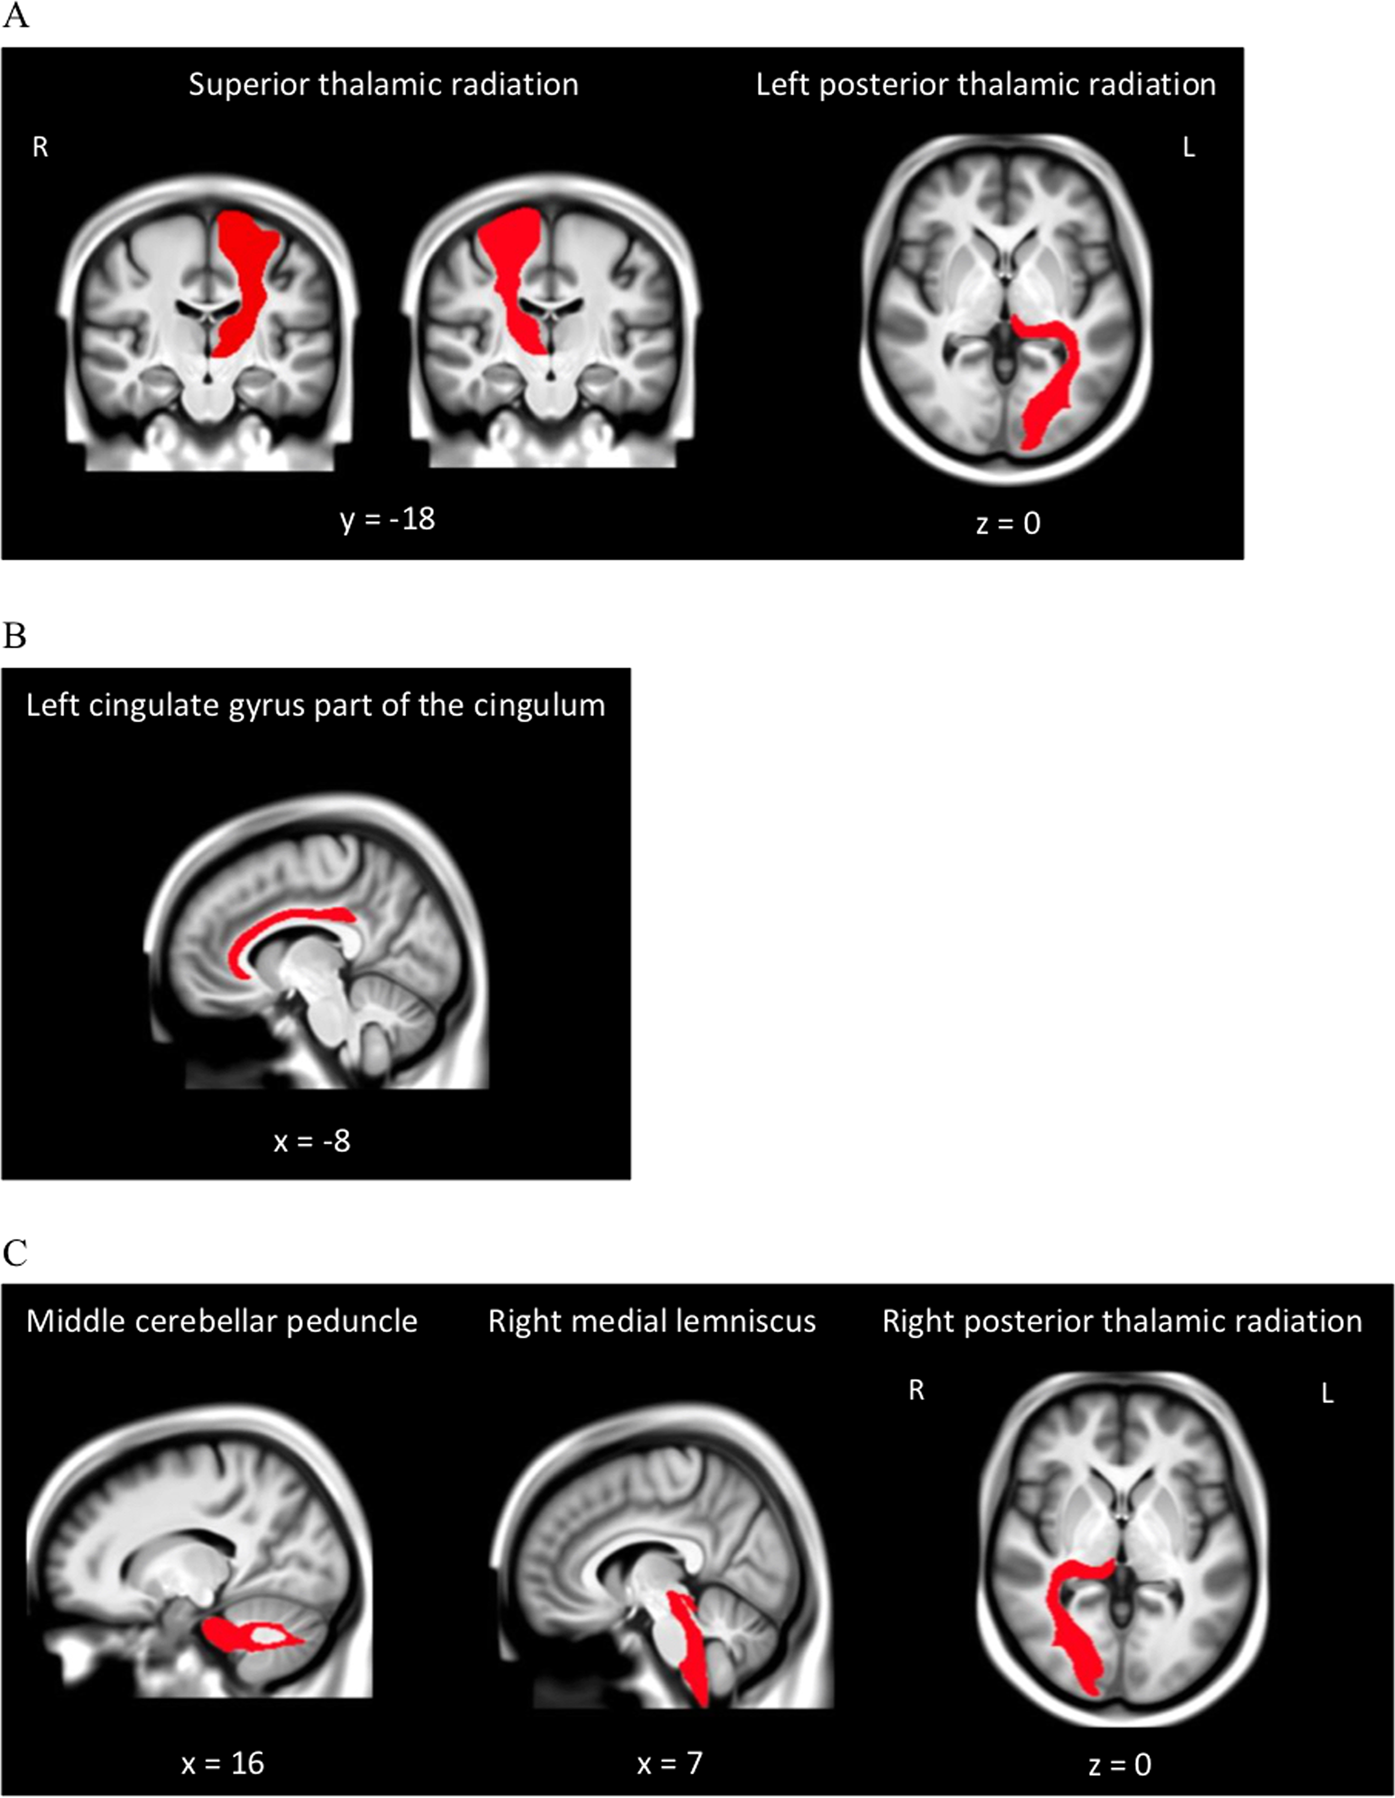

Fig. 2: Group-average structural MRI with significant white matter tracts overlaid, estimated from a subset of UK Biobank study participants (N = 4500).

Images derived from the publically available viewer (https://www.fmrib.ox.ac.uk/ukbiobank/group_means/index.html). Panel A depicts the tracts that were significant in both the fractional anisotropy (FA) and mean diffusivity (MD) analyses. Panel B depicts the tract that was significant in the FA analyses. Panel C depicts the tracts that were significant in the MD analyses.